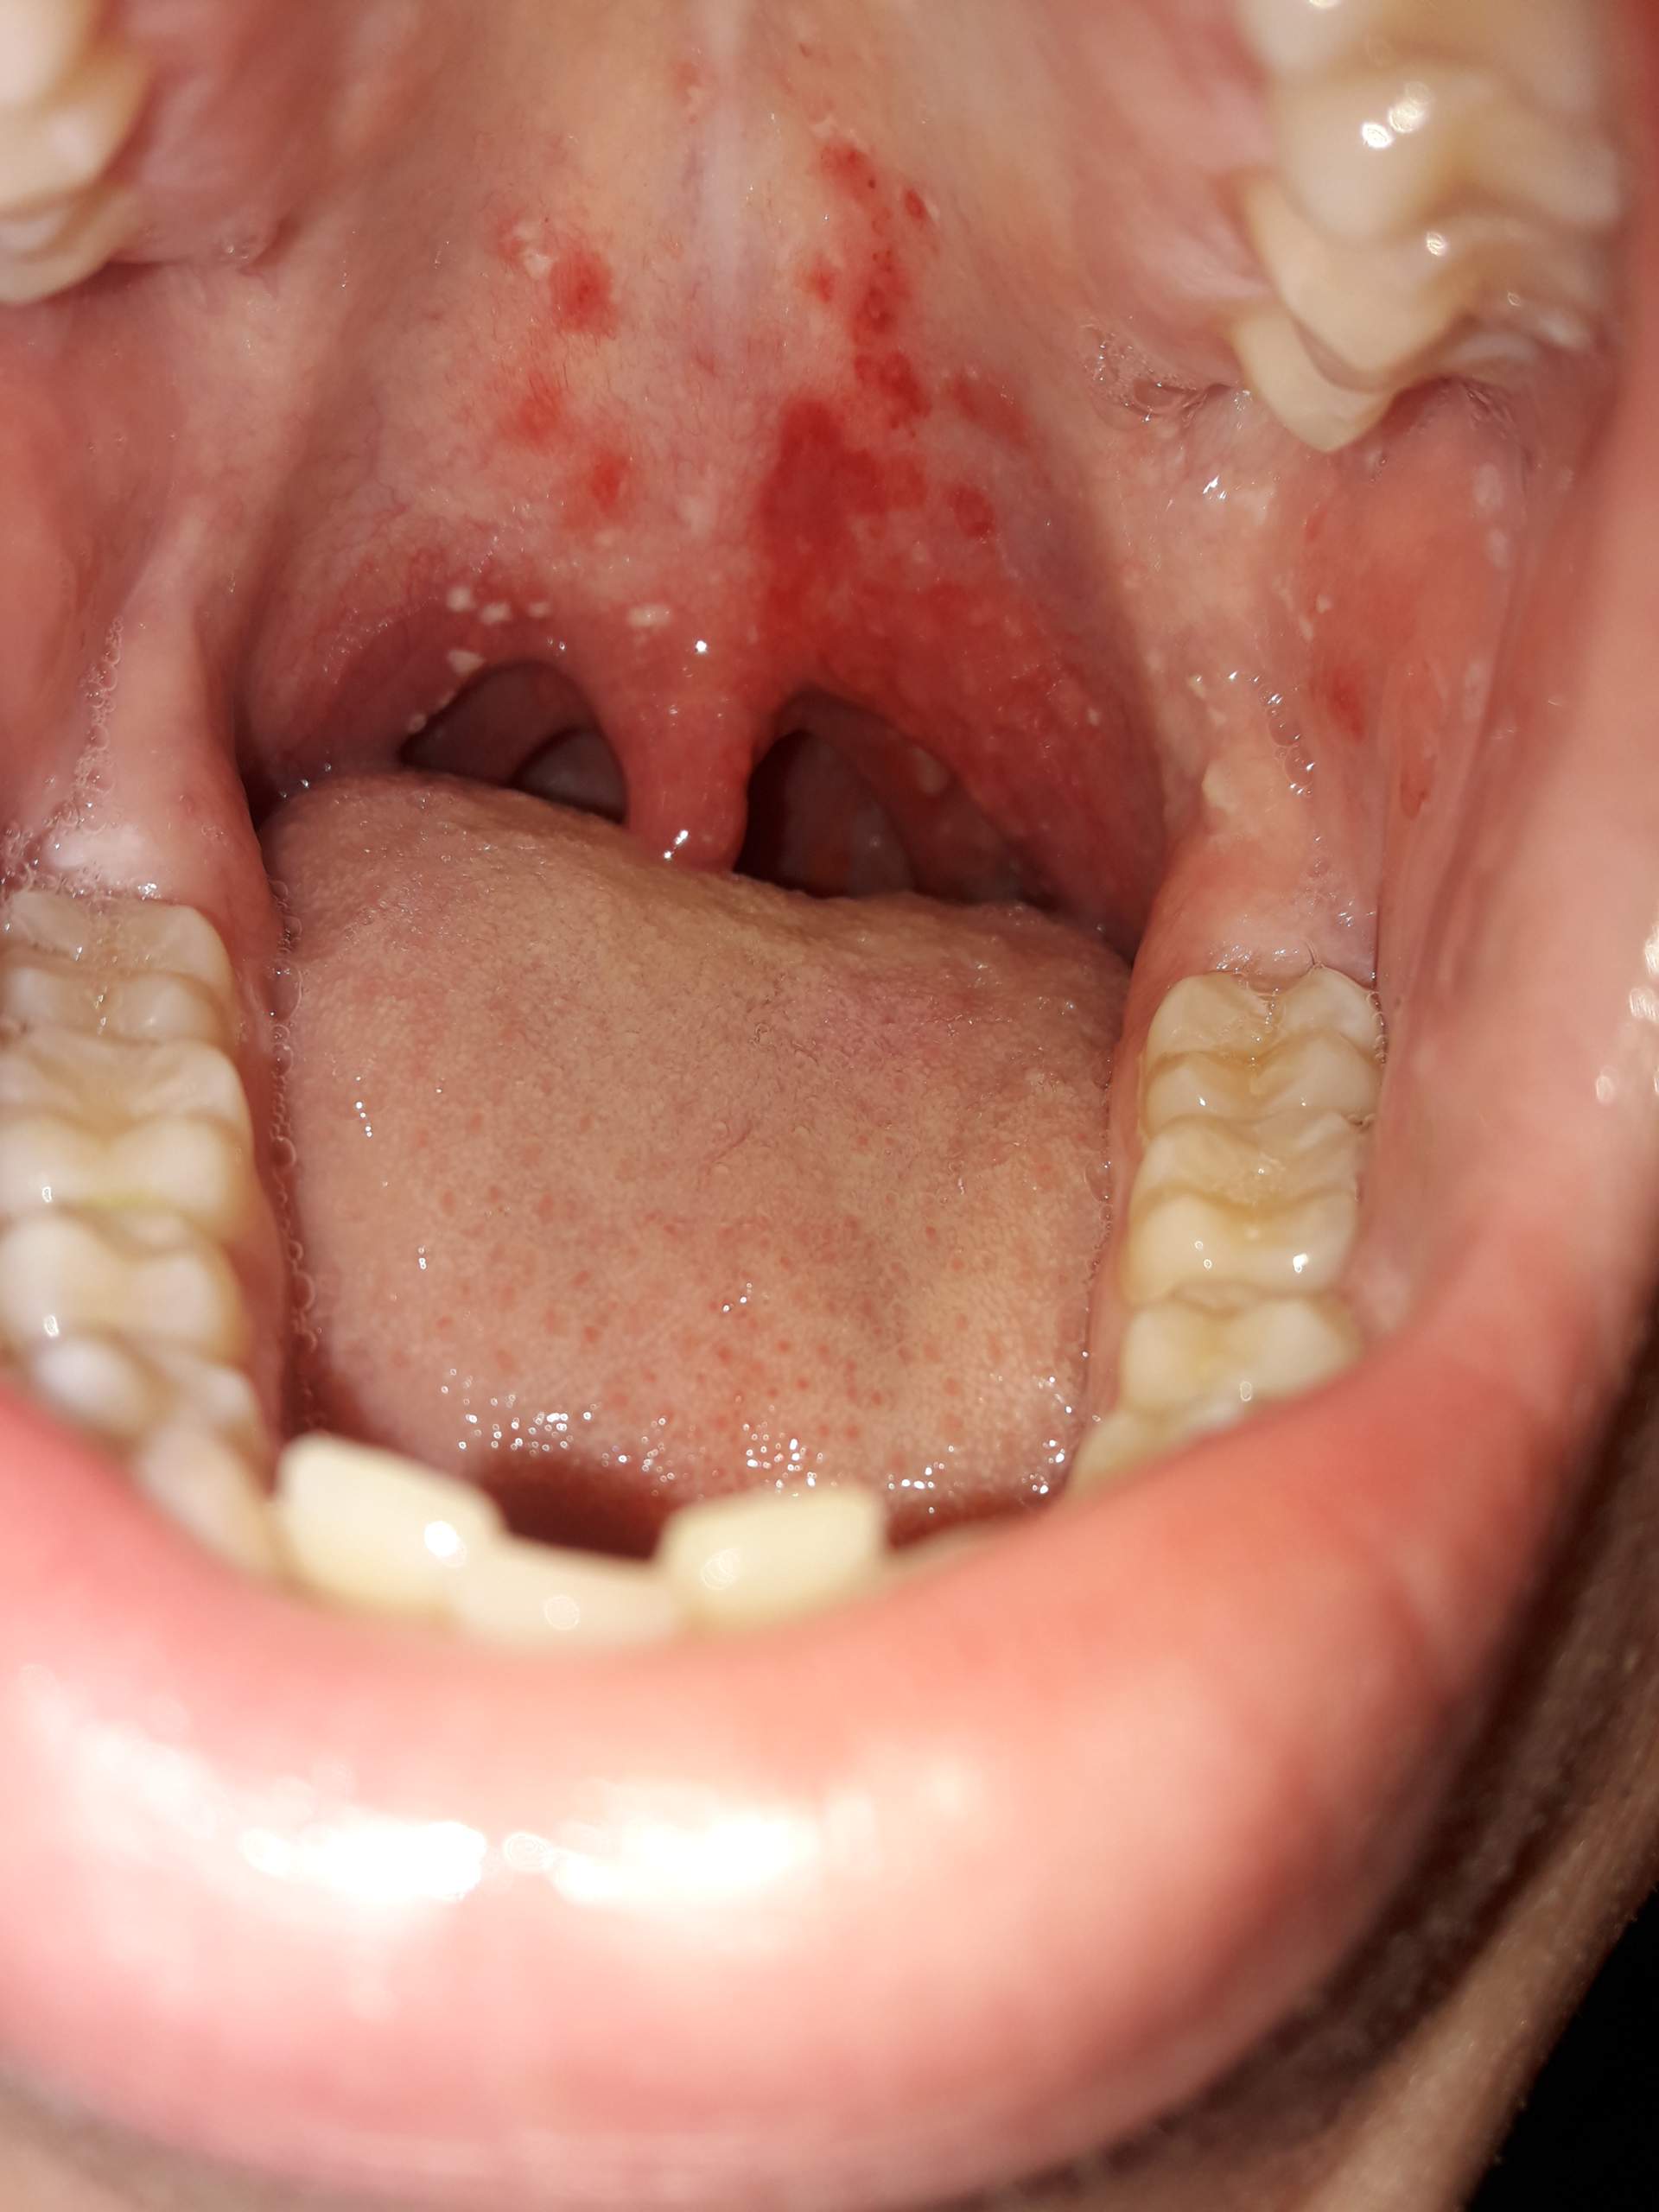

Bläschen und Rötungen im Rachen? (krank, Hals, Mund)

Atrophische Form (Pharyngitis sicca): Häufigste Form der chronischen Rachenentzündung. Die Rachenschleimhaut ist trocken, blass, besonders zart und dünn (atrophisch), firnisartig glänzend und mit etwas zähem Schleim bedeckt. Hypertrophische Form: Die Rachenschleimhaut ist verdickt, gerötet und mit zähem Schleim bedeckt.

Der Rachen oder Pharynx ist der Bereich, der sich vom hinteren Teil des Mundraums und der Nase durch den Hals bis zur Speiseröhre erstreckt. Eine Rachenentzündung kann akut oder chronisch verlaufen: Eine akute Pharyngitis tritt meist im Zusammenhang mit einer Erkältung oder einem grippalen Infekt auf. Schuld daran sind fast immer.

Belag im Rachen und Halsschmerzen, Heilmittel und Antibiotikum